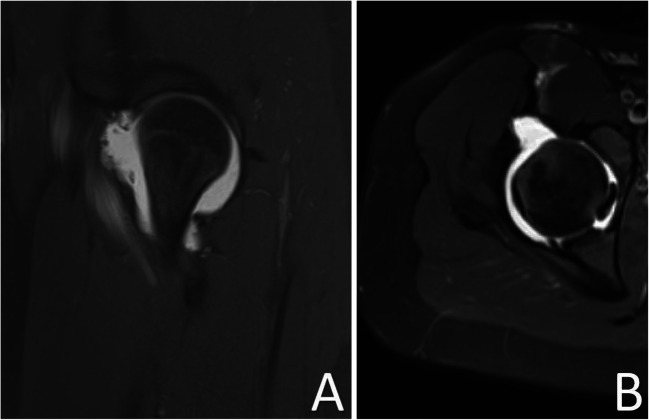

Fig. 3.

A Sagittal and B axial MRI images slices (PD-weighted fat-suppressed) demonstrating a large defect involving the anterior joint capsule measuring 1.7 × 2.7 cm (medial-lateral × cephalad-caudad)